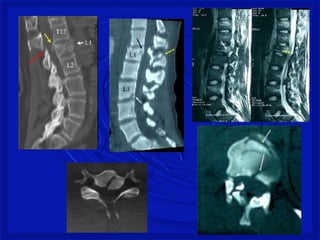

FRATURA COMPRESSÃO TORÁCICA

BAIXA

FRATURA COM LUXAÇÃO COMPLETA –

TORÁCICA BAIXA

LESÕES - COLUNA

Mecanismo de TraumaRaqui- Medular com fratura As lesões ocorrem por: -Flexão, extensão, rotação, compressão por impacto axial ou combinação desses mecanismos.